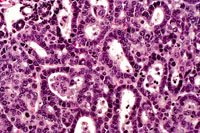

Cholangiocarcinoma next to a more adenomatous lesion with hepatocyte cytological features in a 4-week-old transgenic mouse.